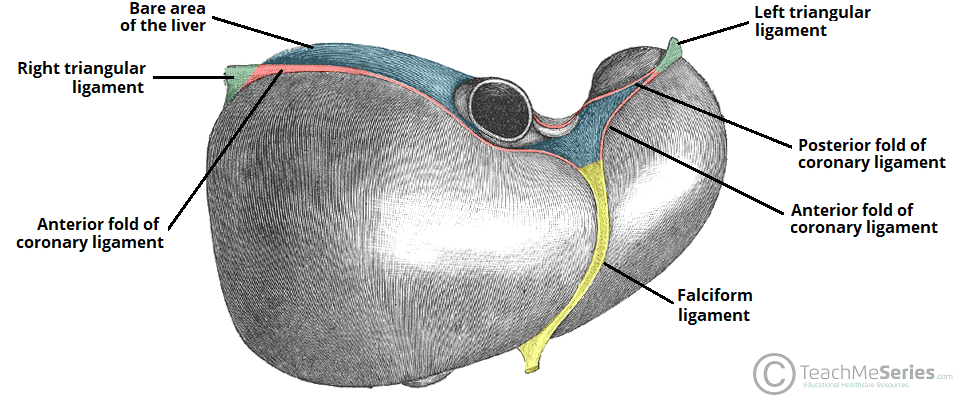

liver

a large organ that plays a crucial role in digestion, metabolism, and detoxification; filters blood, removes toxins and produces bile to help digest fats, and stores glucose vitamins and minerals

right lobe

the largest section of the liver, located on the right side of the abdomen; performs the majority of the liver’s metabolic and detoxification functions; separated from left lobe by the falciform and middle hepatic veins

left lobe

the smaller, flatter of the two major lobes, located on the left side of the body separated from the right lobe by the falciform ligament; responsible for bile production and processing nutrients from the blood

falciform ligament

a sickle-shaped fold of the peritoneum that attaches the liver to the anterior abdominal wall and diaphragm, dividing the liver into its right and left lobes

round ligament

a remnant of the fetal umbilical vein that runs from the umbilicus to the underside of the lower; the free, lower edge of the falciform ligament; also known as ligamentum teres hepatis